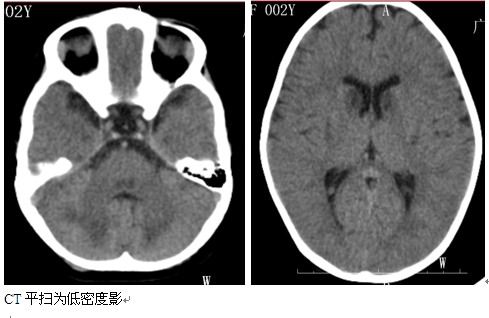

辅助检查:2015年10月13日头颅MRI平扫检查报告:双侧基底节尾状核、豆状核、中脑、双侧丘脑、四脑室周围及小脑半球齿状核周围多发病灶,考虑代谢性疾病可能,以肝豆状核变性可能性大,建议实验室进一步检查。视频脑电图报告:弥漫性慢波增多。线粒体疾病核基因PANEL检测示:患者SURF1基因发现的复合杂合变异分别遗传自受检者父母,父母均为杂合子,符合常染色体隐性遗传方式。(详细见下图)

影像学特点:侧苍白球及导水管周围病变,还可累计丘脑、齿状核、大脑、小脑白质、脊髓、脑皮质,为对称分布,早期肿胀,晚期萎缩。CT平扫为低密度影,一般无强化。MRI T1一般为低信号,T2flair为高信号。慢性期病变可吸收后遗留囊状软化灶,DWI急性扩散期受限,增强后一般强化,MRS显示Cho、Lac升高。